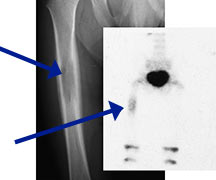

- May arise from any bone and any site within a bone (epiphyseal, metaphyseal, diaphyseal)

- Radiographically variable appearance: may appear benign (geographic) or malignant (permeative or moth eaten)

- Femur